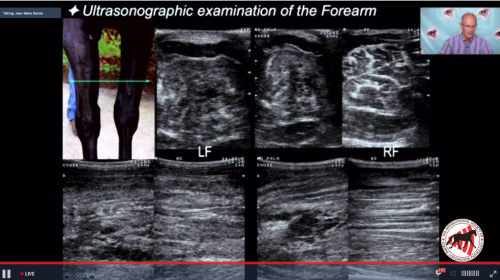

11:00am - Dr. Erik Bergman - Lecture - "The Cranial Neck (ab)Normal Findings"